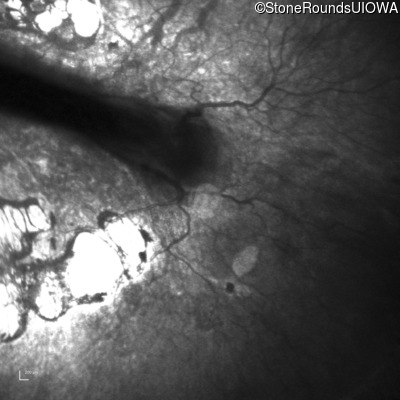

Infrared Fundus Photograph - Right - 20/500

Exemplar